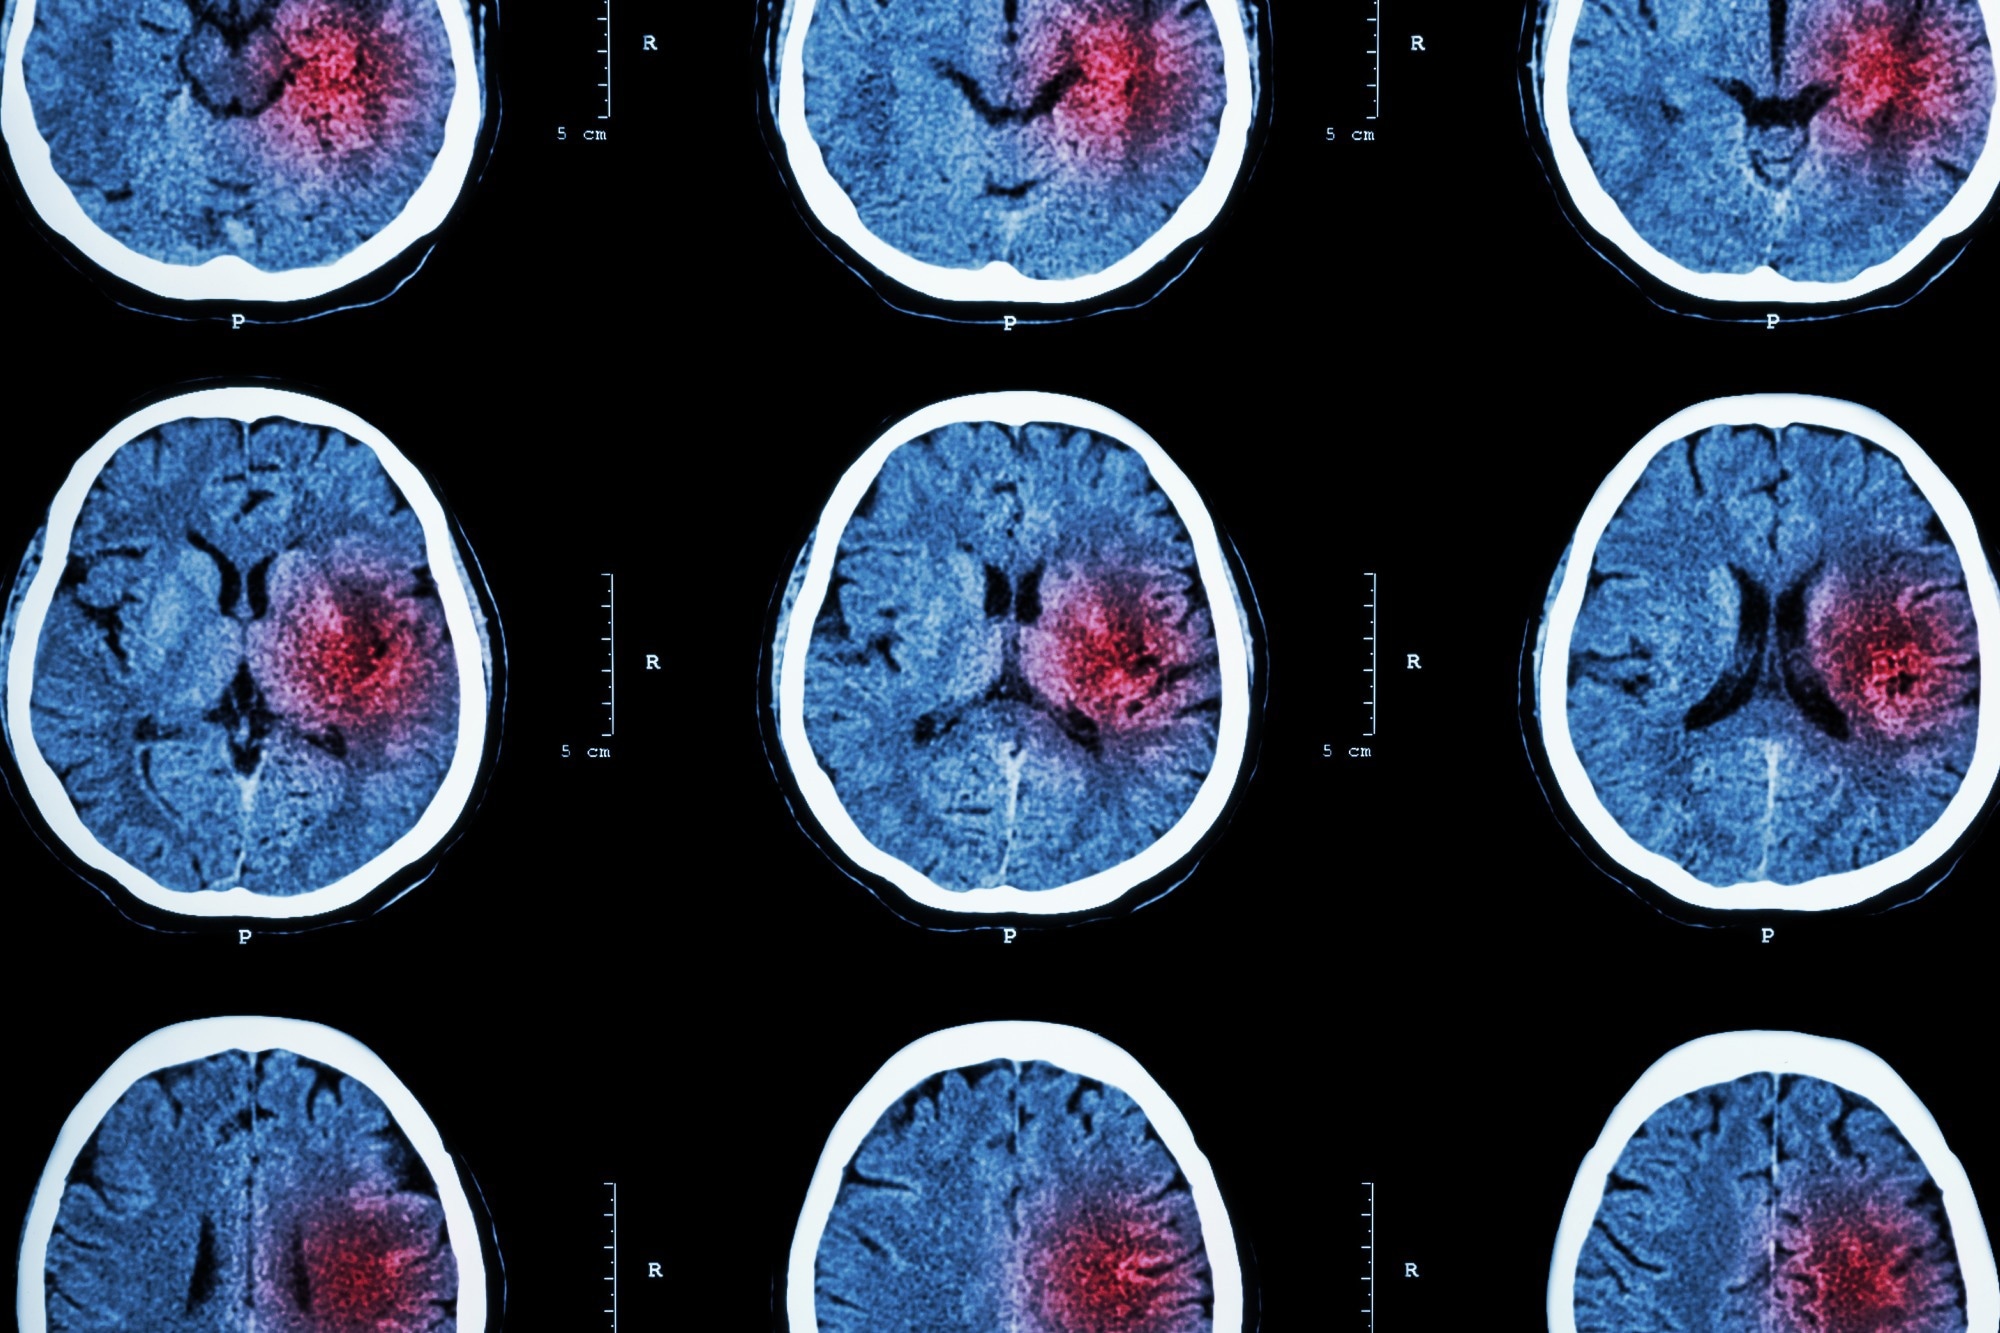

Ein Schlaganfall tritt auf, wenn ein Blutgefäß, das Sauerstoff und Nährstoffe zum Gehirn transportiert, entweder durch ein Gerinnsel blockiert wird oder platzt. Daher gibt es zwei Arten von Schlaganfällen: ischämisch und hämorrhagisch.

Ischämische Schlaganfälle – die am häufigsten vorkommen und 87 % aller Fälle ausmachen – treten auf, wenn ein Blutgerinnsel zu einem Gefäß im Gehirn wandert und die Blutversorgung unterbricht. Dies verhindert, dass das Gehirngewebe Sauerstoff und Nährstoffe erhält, und Gehirnzellen können innerhalb von Minuten absterben.

Die andere Art von Schlaganfall, hämorrhagischer Schlaganfall, ist oft seltener als ischämischer Schlaganfall, kann aber schwerwiegender sein. Diese Arten von Schlaganfällen werden durch ein geplatztes Gehirnaneurysma oder einen Bruch geschwächter Blutgefäße verursacht.